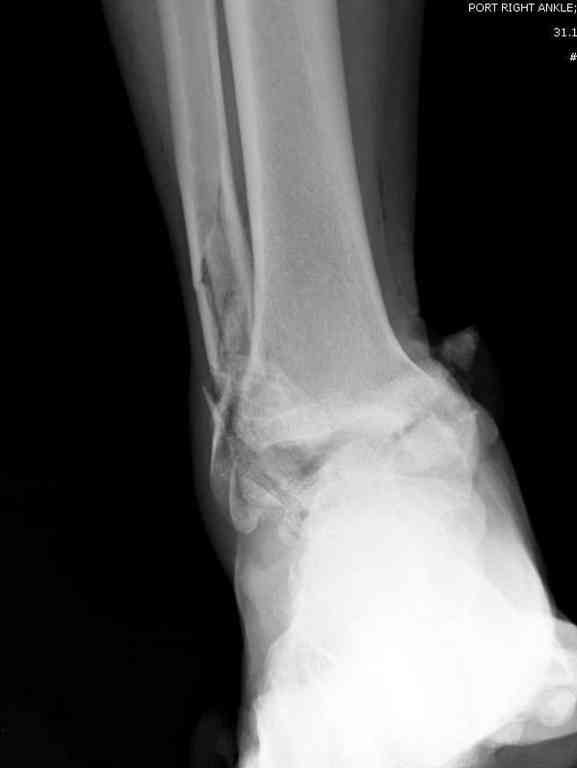

Здесь на фото примеры:

Переломовывих тарана с повреждением медиальной стороны. Через 4 часа после поступления проведена репозиция и фиксация тарана после Irrigation&Debridment. Частичное несращение медиальной лодыжки не беспокоит, вернулся к активному образу жизни. Полная нагрузка разрешена через 11 недель. Финальные снимки через 11 месяцев.